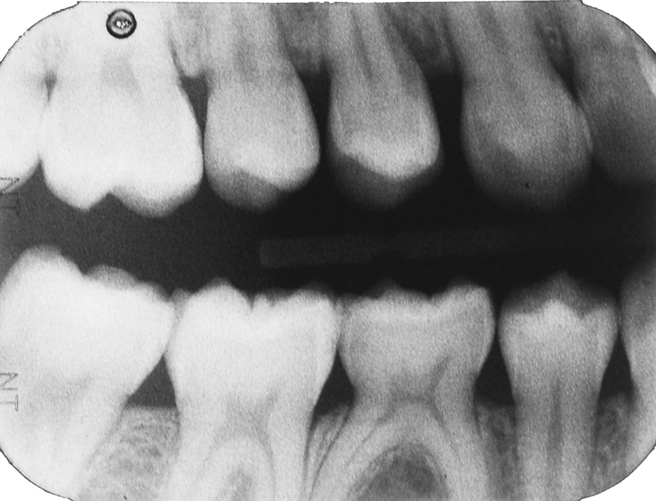

Fig 16. A 15-year-old girl with retained mandibular primary second molar and congenital absence of second premolar (Fig 16). In bitewing film small radiolucencies revealed beginning caries lesions at contact points of primary second molar and adjacent first molar (Fig 17); 12 months later, after initial SDF and 6-month follow-up SDF applications (Fig 18), radiolucencies were not evident.

Figure 16

Fig 17. A 15-year-old girl with retained mandibular primary second molar and congenital absence of second premolar (Fig 16). In bitewing film small radiolucencies revealed beginning caries lesions at contact points of primary second molar and adjacent first molar (Fig 17); 12 months later, after initial SDF and 6-month follow-up SDF applications (Fig 18), radiolucencies were not evident.

Figure 17

Fig 18. A 15-year-old girl with retained mandibular primary second molar and congenital absence of second premolar (Fig 16). In bitewing film small radiolucencies revealed beginning caries lesions at contact points of primary second molar and adjacent first molar (Fig 17); 12 months later, after initial SDF and 6-month follow-up SDF applications (Fig 18), radiolucencies were not evident.

Figure 18